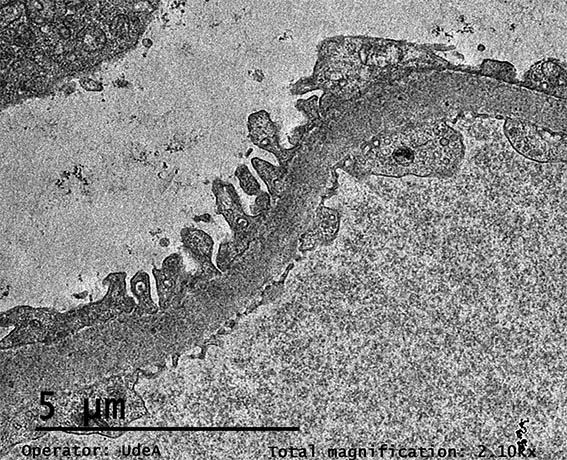

Figura 11. ME, aumento original, X2.100. Procesos podocitarios, membranas basales glomerulares y endotelio normales.

Figura 12. ME, aumento original, X2.100. Paredes capilares glomerulares normales.

Figura 13. ME, aumento original, X2.100.